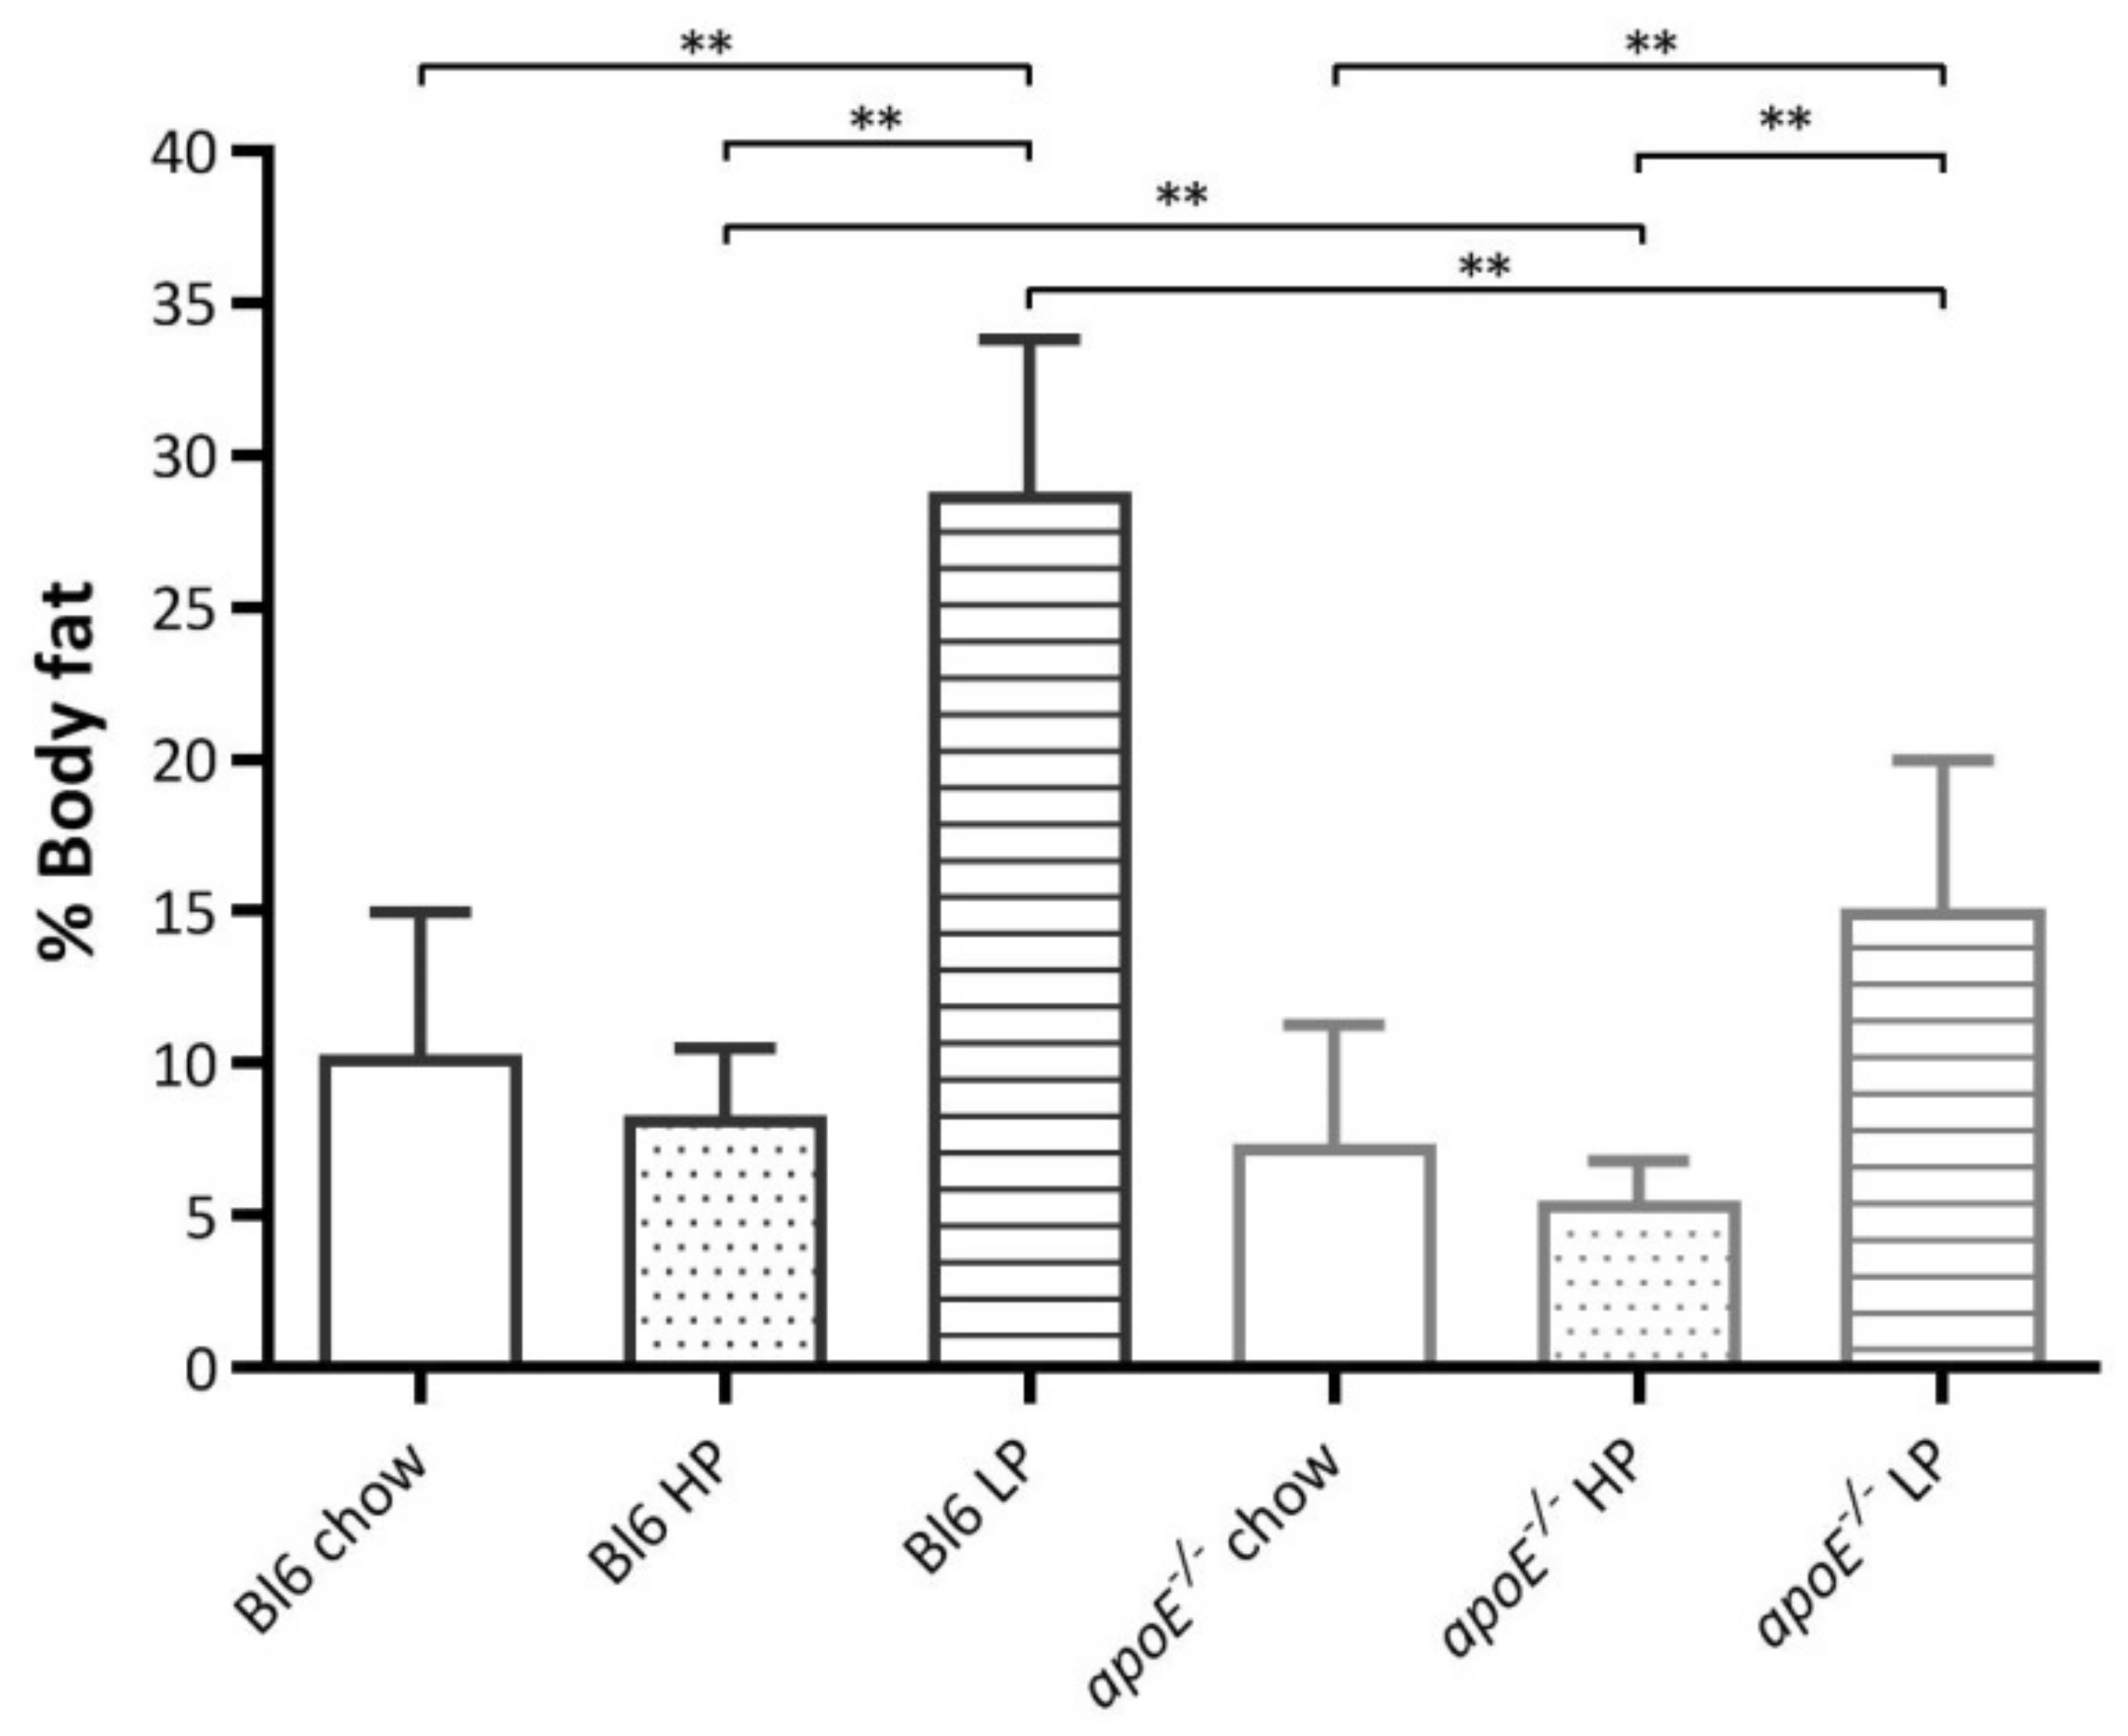

2.4. Effects of Diets on Body Weight and Body Composition